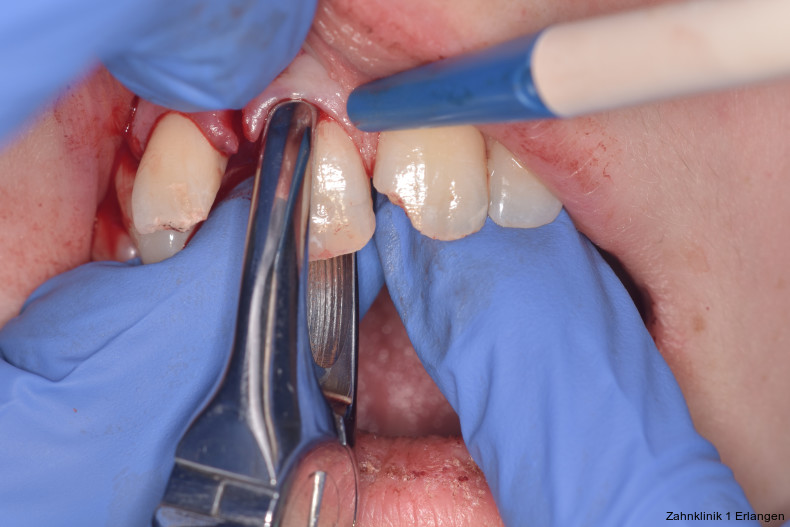

Versorgung von Dislokationsverletzung

Bei ausgeprägten Dislokationsverletzungen stellt die Schädigung des Parodonts die dominierende Verletzung dar, die auch zu Spätfolgen und Komplikationen führen kann. Verletzungen des Endodonts sind im Hinblick auf den Zahnerhalt vergleichsweise unbedeutender, da die Wurzelkanalbehandlung eine Infektion relativ sicher verhindern oder beseitigen kann. Die Erstversorgung schließt im Wesentlichen die Repositionierung und Schienung zur Ruhigstellung der betroffenen Zähne ein.3 Spätestens ab einer Positionsveränderung von 2 mm ist bei Zähnen mit abgeschlossenem Wurzelwachstum sicher von einem irreparablen Schaden der Pulpa auszugehen.2 Wichtig ist es, zeitnah, in der Regel während der Schienungsdauer, die Wurzelkanalbehandlung einzuleiten, um eine bakterielle Besiedelung des Wurzelkanals zu verhindern. Dabei reicht es zunächst aus, den Zahn zu eröffnen, desinfizierend zu spülen und eine medikamentöse Einlage einzubringen. Wird dies unterlassen, entwickeln sich bei entsprechender parodontaler Schädigung infektionsbedingte Resorptionen, die rasch fortschreiten und innerhalb relativ kurzer Zeit bis zum Zahnverlust führen können.